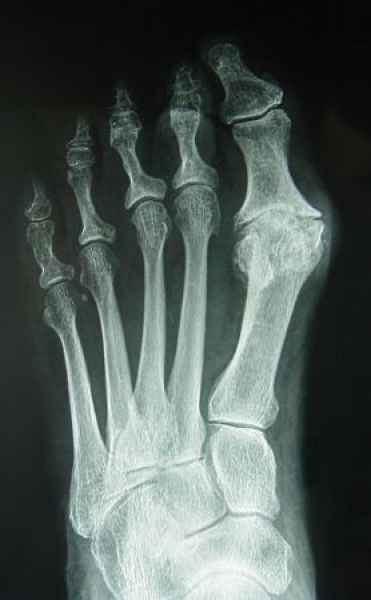

La marcha no solo es característica de la especie humana sino también de cada persona, y más aún varía según el estado de ánimo del momento. Una patología en los pies, se traduce en el rostro, en el ánimo, en el psiquismo. No sólo el dolor produce estos efectos, también un pie deformado o poco estético. En nuestra sociedad, la estética constituye un valor muy apreciado y estas alteraciones causan vergüenza fundamentalmente en las mujeres, que esconden en la playa sus pies en la arena y no pueden usar calzados elegantes.

Tanto la estructura del pie como su funcionalismo que es la marcha, pueden ser asiento y manifestación respectivamente de alteraciones locales ó sistémicas, por lo que su cuidadoso examen resulta de extrema utilidad diagnóstica.